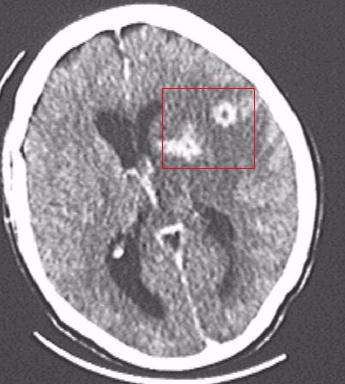

Формы токсоплазмоза. Осложнения

Сначала рассмотрим подробнее, к чему приводит запущенный токсоплазмоз. Симптомы у человека (фото на пленке посредством МРТ в разрезе) осложненного течения болезни в виде образований в мозговых оболочках просматриваются на нижеприведенном рисунке. Зона поражения обозначена красным квадратом, и она свидетельствует о развитии гнойного менингоэнцефалита. Этому состоянию могут сопутствовать осложнения — слепота, истощение, паралич. Смерть наступает от обширного и стремительно развивающегося поражения головного мозга.